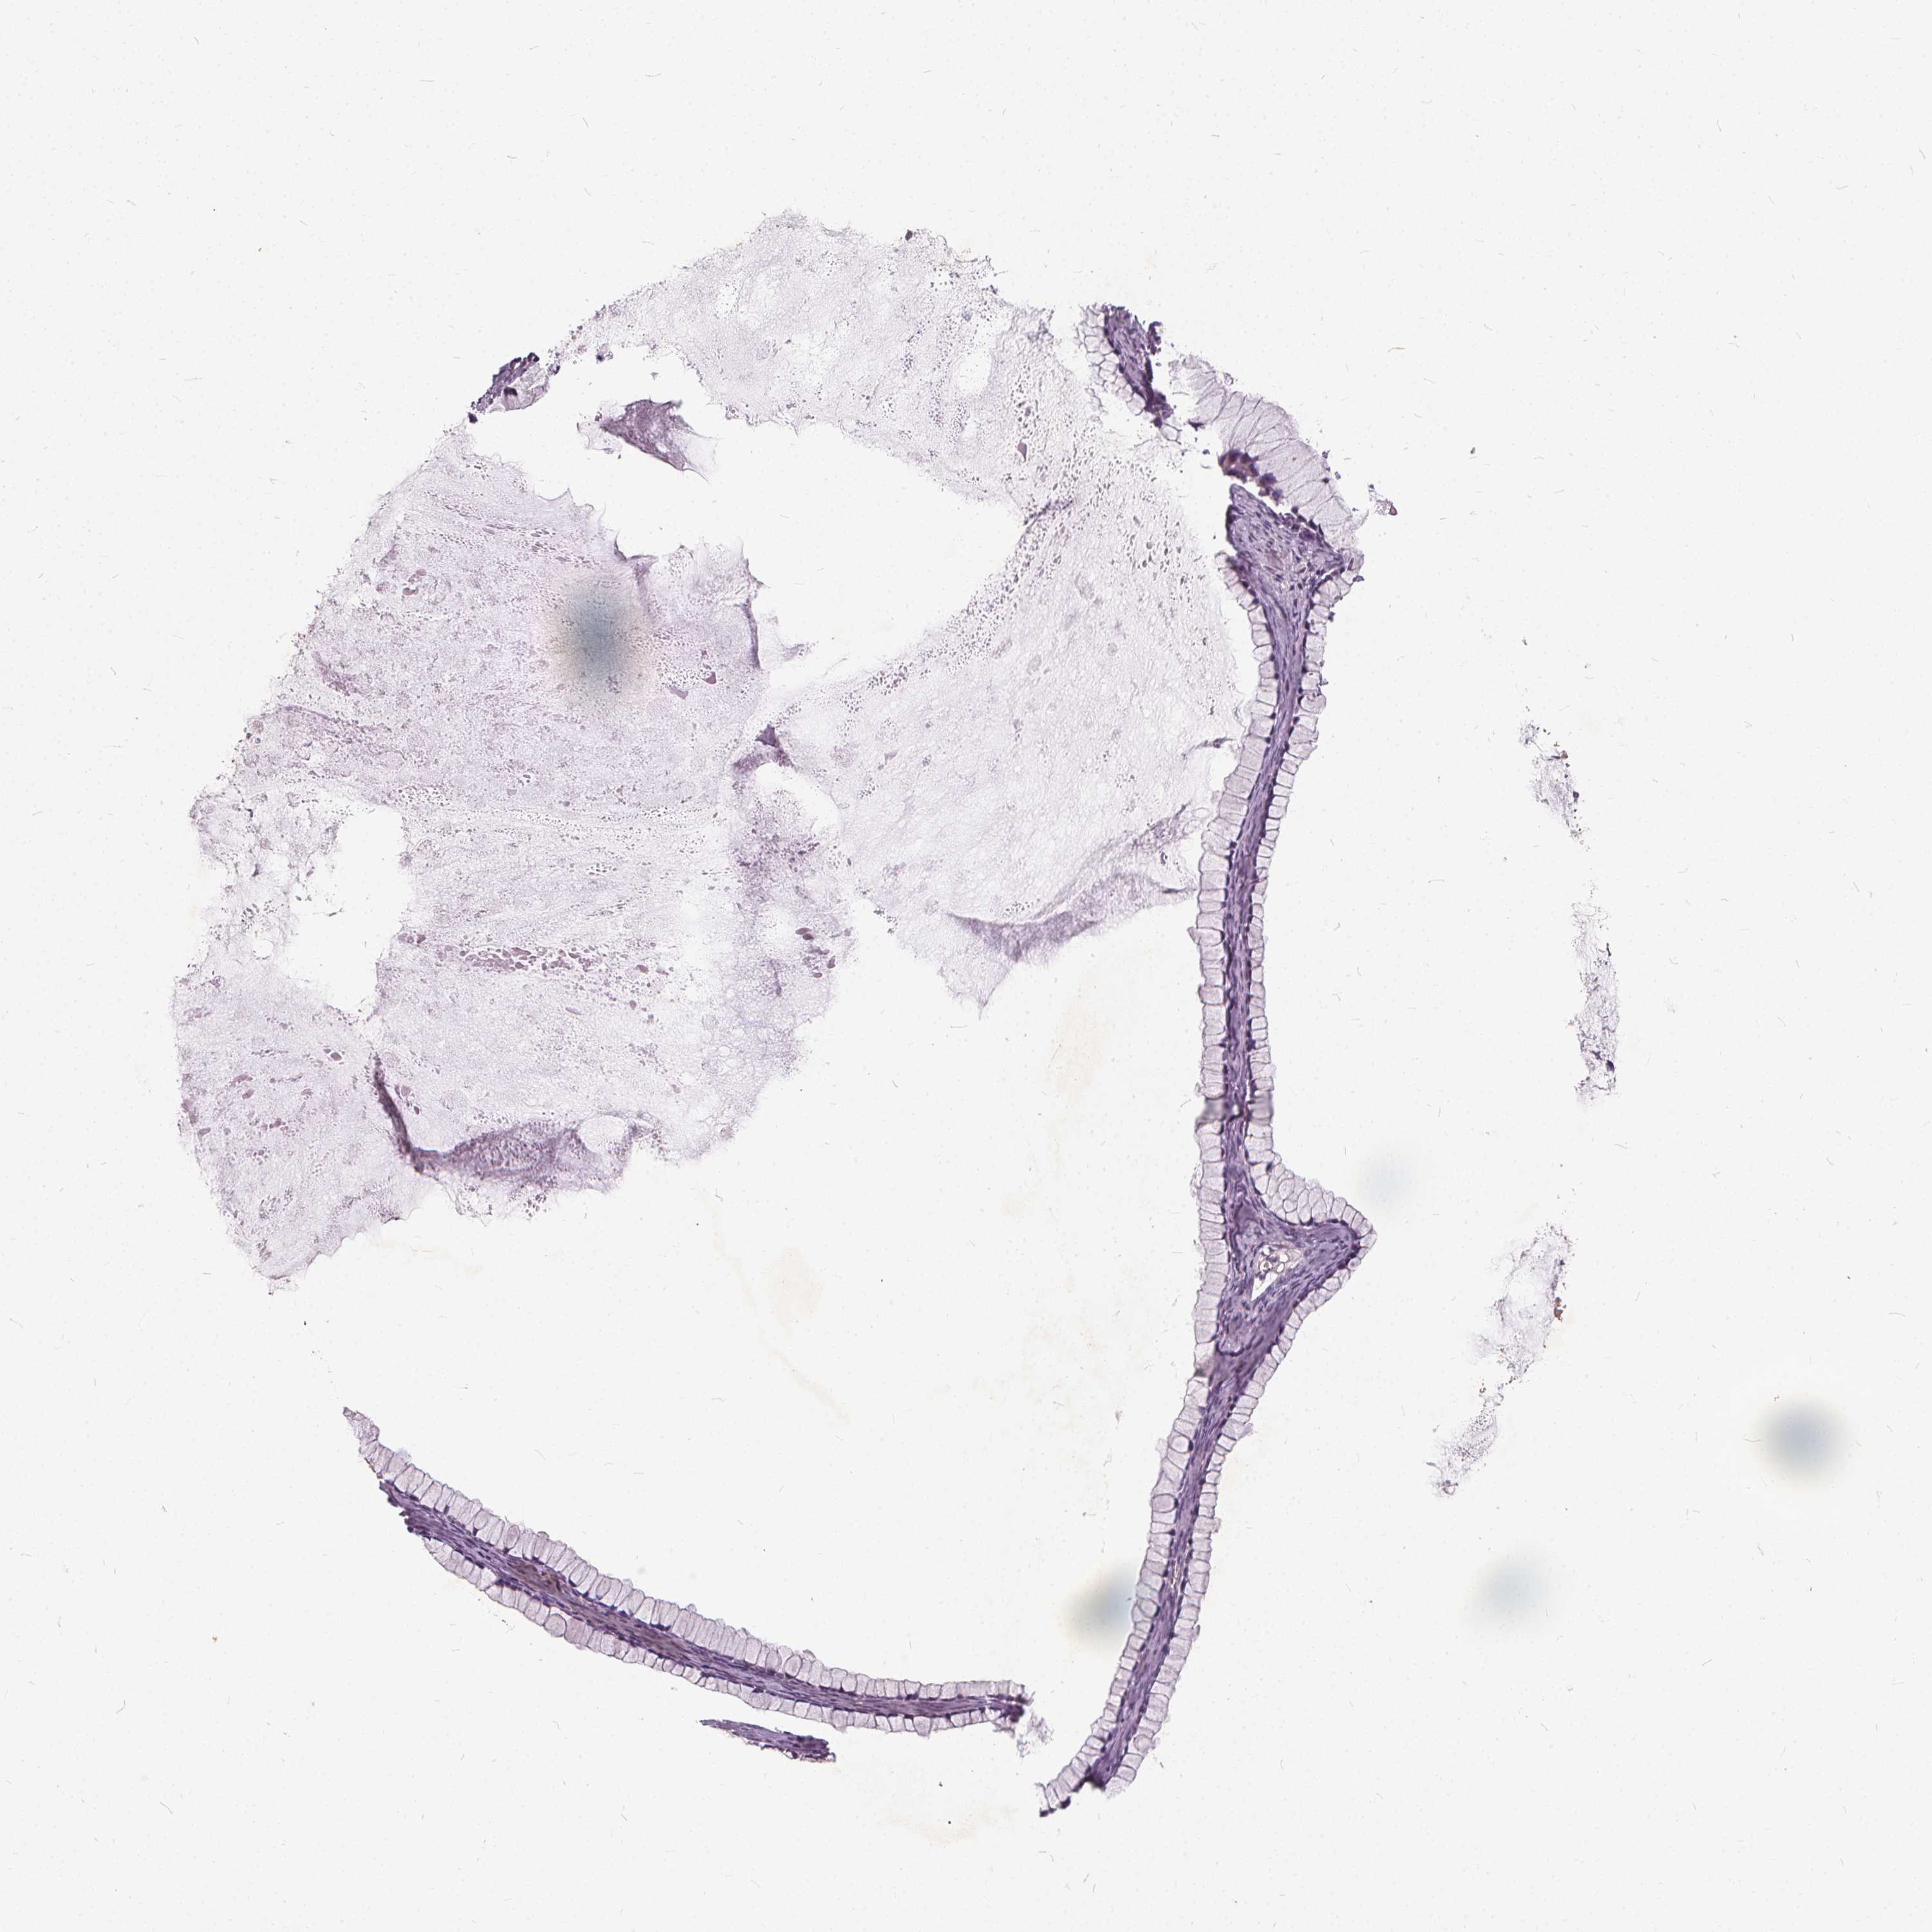

OVARIAN CANCER - Protein expressioni

A mouse-over function shows sample information and annotation data. Click on an image to view it in a full screen mode. Samples can be filtered based on level of antibody staining by selecting one or several of the following categories: high, medium, low and not detected. The assay and annotation is described here.

Note that samples used for immunohistochemistry by the Human Protein Atlas do not correspond to samples in the TCGA dataset.

Antibody stainingi

Antibody staining in the annotated cell types in the current human tissue is reported as not detected, low, medium, or high, based on conventional immunohistochemistry profiling in selected tissues. This score is based on the combination of the staining intensity and fraction of stained cells.

Each image is clickable and will lead to virtual microscopy that enables deeper exploration of all samples and also displays staining intensity scores, fraction scores and subcellular localization as well as patient and tissue information for each sample.

Antibody HPA065937

Staining

High

Medium

Low

Not detected

Intensity

Strong

Moderate

Weak

Negative

Quantity

>75%

75%-25%

<25%

None

Location

Nuclear

Cytoplasmic/membranous

Cytoplasmic/membranous,nuclear

Cystadenocarcinoma, serous, NOS

Cystadenocarcinoma, mucinous, NOS

Carcinoma, endometroid